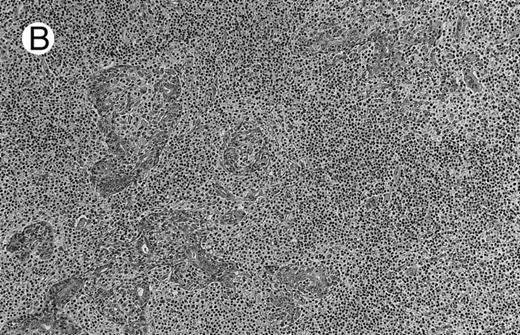

Low-grade marginal zone B-cell lymphoma (MZL; REAL classification)9 comprised the largest number of cases (n = 12). Nine of them were low-grade MALT type lymphomas involving parotid, stomach, bronchus, buccal mucosa, and skin. The histological pattern was relatively homogeneous, showing diffuse lymphoid infiltrates that included small lymphocytes with round nuclei or with plasma-cell differentiation and/or centrocyte-like cells with indented nuclei (Fig 1A). Lymphoepithelial lesions were observed in each case, regardless of the tissue involved (Fig 1B). Monocytoid cells characterized by a larger cytoplasm and a slightly irregular nucleus were mixed with centrocyte-like cells in 2 cases of MALT lymphoma arising in the parotid (cases no. 3 and 15). There were also scattered occasional large cells (centroblast or immunoblast). In cases no. 3, 6, and 15, remnants of germinal centers with partial follicular colonization were observed (Fig 1C). Beside these 9 low-grade-type mucosal lymphomas, 3 nodal lymphomas (cases no. 8, 10, and 14) had histological features similar to that of low-grade MALT type lymphoma because they showed a typical lymphoplasmacytoid infiltration with a variable proportion of blasts. In 2 cases, the presence of numerous immunoblasts or centroblasts, mixed with small lymphoplasmacytoid cells or plasma cells, indicated an evolution to a more aggressive lymphoma (Fig 1D). The third nodal lymphoma showed a small lymphocytic or lymphoplasmacytoid diffuse infiltrate associated with intrasinusal large nests of monocytoid cells. This histological picture is characteristic of monocytoid B-cell lymphoma (MBLC; Fig 1E).

NHL associated with SS (hematoxylin-eosin stains). (A) Case no. 13. Low-grade B-cell lymphoma of MALT type in the stomach, composed mainly of centrocyte-like cells with a few small lymphocytes and plasma cells. (B) Case no. 15. Low-grade B-cell lymphoma of MALT type in the parotid. Lymphoepithelial lesions are numerous, surrounded by centrocyte-like cells. (C) Case no. 6. Remnants of a germinal center in a low-grade B-cell lymphoma of MALT type in the parotid.

(D) Case no. 10. Immunocytoma in lymph node. The infiltrate is composed of small lymphocytes, plasma cells and blasts. (E) Case no. 14. Monocytoid B-cell lymphoma in a cervical lymph node with a monocytoid component located in dilated sinuses.